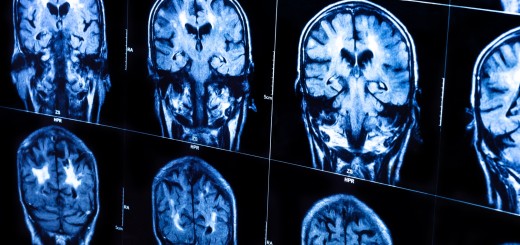

Undoubtedly the most interesting conversation I had at SXSW was with Dr Ted Berger, who is working on a brain implant to make life better for people who have problems with long-term memory – and the science behind it is fascinating. Berger explained to me how people with conditions like epilepsy and alzheimers can suffer problems with their hippocampus, the part of the brain that turns short-term memories into longterm ones. Essentially, our initial memories of an event are binary electrical codes that are filtered through the hippocampus to another part of the brain for longterm storage. What Berger, who…